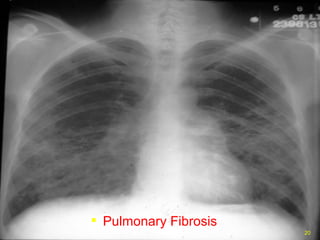

Pulmonary Fibrosis